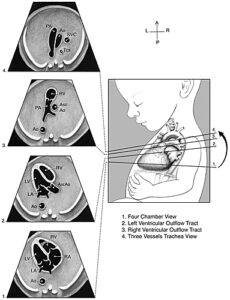

Основные плоскости сканирования могут предоставить полезную диагностическую информацию о сердце плода (цифры 1? — 3?? ) . Должны быть получены следующие сердечные изображения:

Унифицированные поперечные плоскости сканирования для эхокардиографии плода включают в себя оценку 4 сегментов — камер ( 1 ) , артериальных путей оттока (2 и 3 ) , а вид 3 — судно и трахеи ( 4 ) . Ао показывает нисходящую аорту ; Asc Ао , восходящей аортой ; LA , левое предсердие ; LV , левый желудочек ; PA, легочной артерии ; RA , правое предсердие ; RV , правый желудочек ; и Тra ,